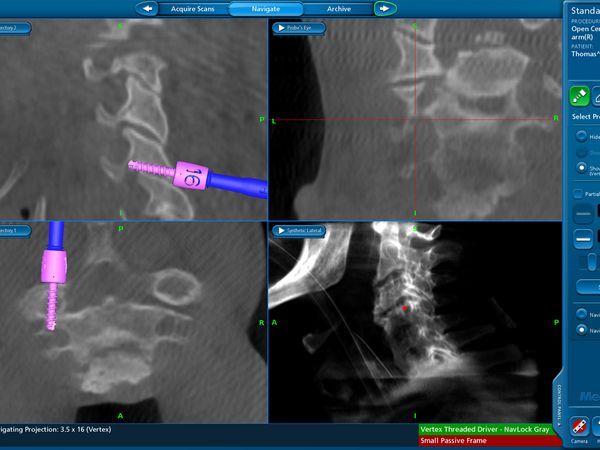

Νευροπλοήγηση με Stealth Station και διεγχειρητική απεικόνιση με 0 ARM.

Διεγχειρητική απεικόνιση οπίσθιας σπονδυλοδεσίας ΑΜΣΣ με O ARM